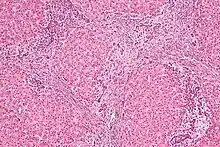

| Micrograph of focal nodular hyperplasia. H&E stain. | |

Focal nodular hyperplasia's most recognizable gross feature is a central stellate scar seen in 60–70% of cases. Microscopically, a lobular proliferation of bland-appearing hepatocytes with a bile ductular proliferation and malformed vessels within the fibrous scar is the most common pattern. Other patterns include telangiectatic, hyperplastic-adenomatous, and lesions with focal large-cell dysplasia.[4] Rarely, these lesions may be multiple or can occur as part of a syndrome with hemangiomas, epithelioid hemangioendothelioma, hepatic adenomas, fibrolamellar hepatocellular carcinoma, vascular malformations of the brain, meningiomas, and/or astrocytomas.[4]